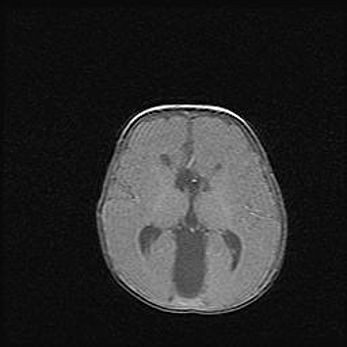

Киста прозрачной перегородки.

Возраст: 8 дней

Вес: 3800 г

Пол: мужской

Окружность головы: 36 см

Срок гестации: 40 недель

Наиболее распространенными причинами появления кист прозрачной перегородки являются:

- аномальное внутриутробное развитие плода. Например, у недоношенных детей киста встречается в 100% случаев и только от своевременной диагностики и лечения зависит ее дальнейшая динамика,

- травмы головы, сопровождающиеся кровоизлиянием, сотрясением головного мозга,

-  инфекционные заболевания и воспаления головного мозга.